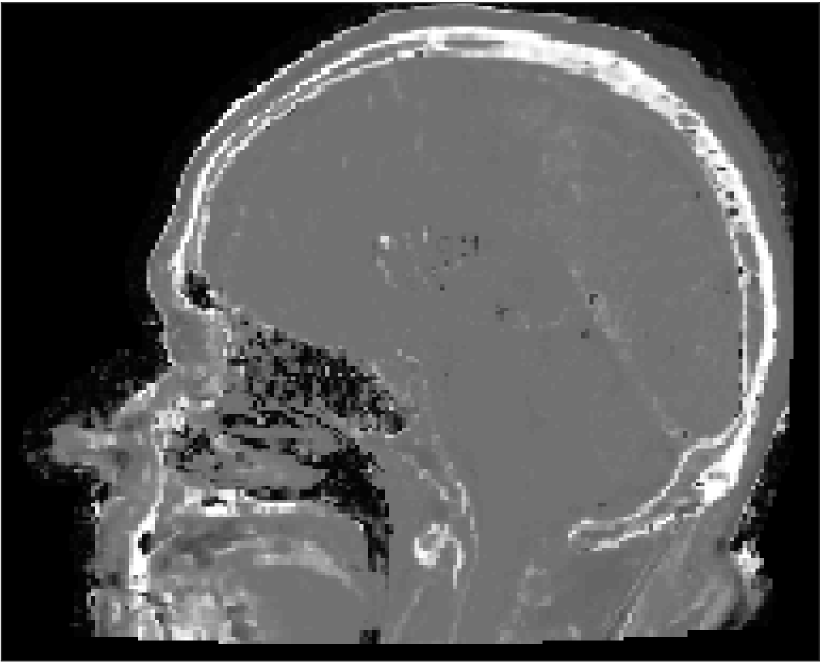

All MR images were acquired with a 1.5 T Siemens Espree scanner. The UTE images were reconstructed to 192×192×192192192192192\times 192\times 192 voxel bitmapped images with an isotropic resolution and a voxel size of 1.33 mm. The UTE sequences sampled the k-space radially with 30 000 radial spokes. CT images were acquired with a tube voltage of between 120 kV and 130 kV on either a GE Lightspeed Plus, Siemens Emotion 6 or GE Discovery 690. The in-plane pixel size varied between 0.48 mm to 1.36 mm and the slice thickness between 2.5 mm and 3.75 mm. Images of the same patient were co-registered and resampled to achieve voxel-wise correspondence between all five modes. A binary mask excluding most of the air surrounding the head was computed from the images and used to remove unnecessary data. Furthermore, to reduce the execution time of the parameter estimation phase, only 11 slices in the middle of the head of each patient was used during the parameter estimation phase, but all slices were used during the prediction phase (s-CT generation). Additional details concerning the data can be found in Johansson et al. [16]. Data from one slice of a patient is shown in Figure 3.

Refer to caption

(a) Binary mask

(b) CT

(c) First echo, 10superscript1010^{\circ}

(d) Second echo, 10superscript1010^{\circ}

(e) First echo, 30superscript3030^{\circ}

(f) Second echo, 30superscript3030^{\circ}

Figure 3: Binary data mask (panel a), CT image (panel b), The four MRI UTE sequences (panels c-f).